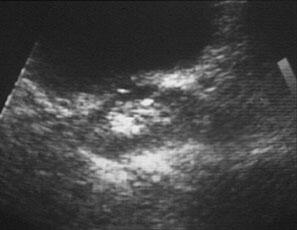

L'activité biologique de la quercétine dépend de sa biodisponibilité qui varie largement en fonction des sources dont elle est extraite ou, plus précisément, selon les caractéristiques de la chaîne sucrée de sa molécule. Des chercheurs hollandais ont comparé la biodisponibilité de quercétine provenant d'oignons et de thé.

Dans cette étude on a demandé à neuf sujets de suivre une alimentation sans quercétine pendant douze jours et on leur a donné les quatrième, huitième et douzième jours un supplément d'oignons frits (riches en glucosides de quercétine équivalents à 89 mg de quercétine) ou du thé (riche en rutinoside de quercétine équivalent à 100 mg de quercétine) ou 100 mg de quercétine. Les chercheurs ont constaté que l'absorption des glycosides de quercétine était de 52 %, celle du rutinoside de quercétine de 17 % et celle de l'aglycone de quercétine de 24 %21.

Une autre étude a comparé chez le cochon la biodisponibilité de différents glycosides de quercétine (dont l'isoquercitrine) et de l'aglycone de quercétine. Les résultats ont montré que l'isoquercitrine avait une biodisponibilité très supérieure à celles des autres formes.

Cette biodisponibilité était également dépendante de facteurs alimentaires. Ainsi, la consommation de viande stimulait son absorption de façon significative22.